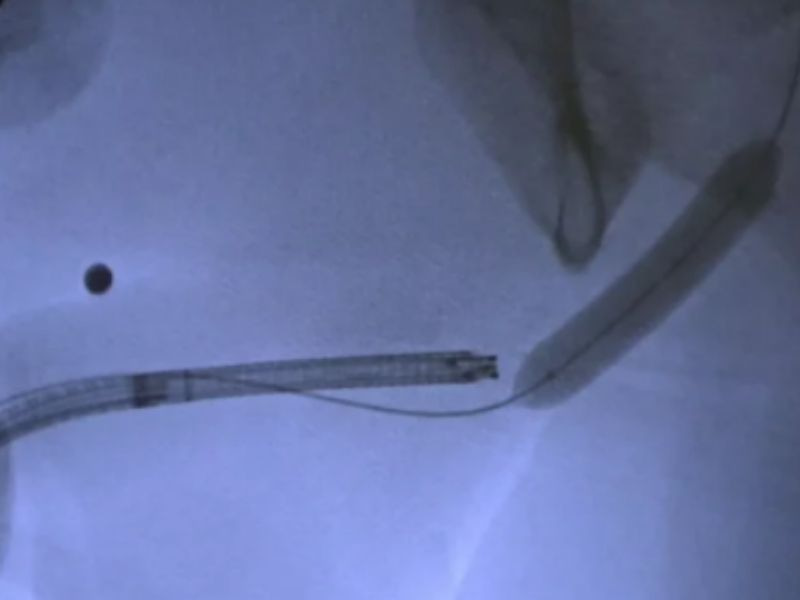

- Darlık bölgesine ulaşıldığında, ilaç kaplı balon şişirilir.

- Balon dar yeri açar ve aynı anda ilacı dokuya bırakır.